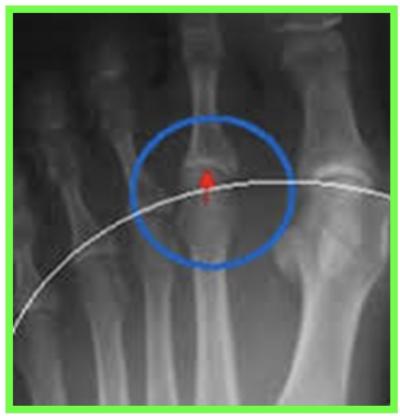

Radiographie des pieds face et profil en charge +++ avant consultation d’un spécialiste

Étude de l’architecture global du pied, de l’état articulaire à la recherche d’une arthrose, fracture de contrainte, et mesure des angles

Le pincement de l’interligne articulaire et les ostéophytes ci-dessus sont caractéristiques de l’hallux rigidus